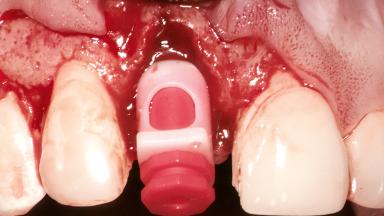

Replacement of a Maxillary Right Central Incisor Using an Early Loading Protocol

A healthy 26-year-old woman was referred for evaluation and treatment of her failing maxillary right central incisor (tooth 11). She reportedly traumatized the tooth at about age 9 and subsequently had repeated conventional and surgical endodontic procedures and fixed restorations. Despite these procedures, she had recurrent fistulas in the apical mucosa and a mid-facial pocket of 7 mm with suppuration. All other sites on the tooth probed 3 mm without inflammation. She presented with a medium biotype with triangularlyshaped teeth and a moderately high smile line, showing all of her papillas and a few millimeters of marginal gingiva in a full smile.Ceramic veneers were present on teeth 12, 21, and 22, and they were known to be somewhat bulky, eventually requiring replacement. She had a strong desire to avoid additional tooth preparation and would not consider a fixed dental prosthesis to replace tooth 11.

Bone Augmentation Horizontal|Simultaneous

Augmentation Materials Autogenous chips|Membrane

Soft Tissue Grafting Simultaneous

Bone Volume Deficient horizontally, allowing simultaneous augumentation